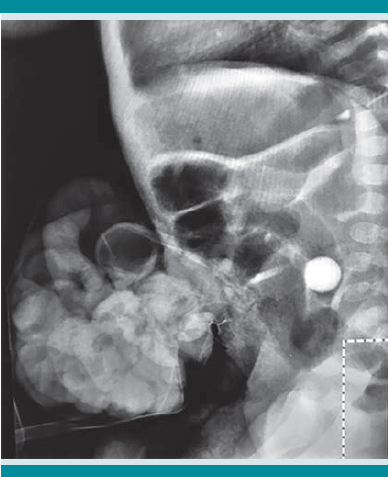

Los reportes de los exámenes de laboratorio y gasometría sin alteraciones. En las radiografías toracoabdominal antero-posterior y lateral de abdomen (Figuras 3 y 4) se observó una canica en la cavidad abdominal. Con lo anterior se estableció el diagnóstico de ruptura de saco herniario umbilical asociada con la colocación de un cuerpo extraño, con evisceración.

Se realizó intervención quirúrgica de urgencia, con plastia e introducción de las asas intestinales, sin contratiempos ni complicaciones (Figura 5 y 6). Los hallazgos quirúrgicos revelaron la existencia de un objeto extraño en la cavidad (canica) y las asas del intestino delgado evisceradas. El tamaño del defecto de la pared era de 2 cm de diámetro, a la altura del ombligo.